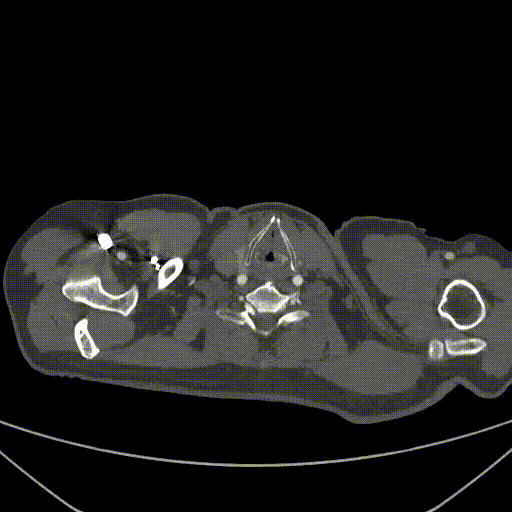

★ Case 4

男性,71岁,间断胸痛半年,加重7+天

高血压1+年,收缩压最高160+ mmHg

既往史和手术史:保守治疗1+月,弓部血肿增厚,胸痛加重

夹层动脉瘤CTA:主动脉夹层(非A非B型),累及主动脉弓至腹腔干发出平面以上腹主动脉,真腔小,假腔大;主动脉弓及左颈总动脉、左锁骨下动脉近端管径增粗,合并壁内血肿

术前影像

股-升主动脉支架

颈-无名动脉+左颈总动脉支架

股-弓部+左锁骨下动脉支架

术后复查